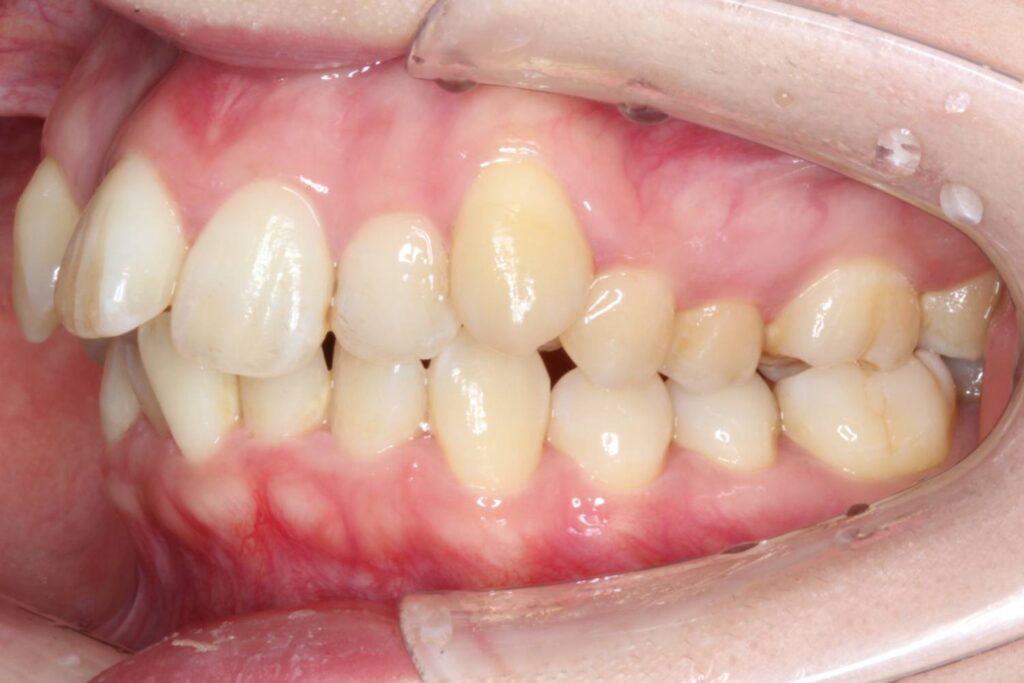

After

治療後は上顎の前歯が引っ込み、歯のがたつきも改善しています。

そうすることで、見た目だけではなく、前歯でものが噛み切りやすい機能的な歯並びが達成されました。

上顎の歯のみを抜歯していますが、噛み合わせのバランスには全く問題ありません。